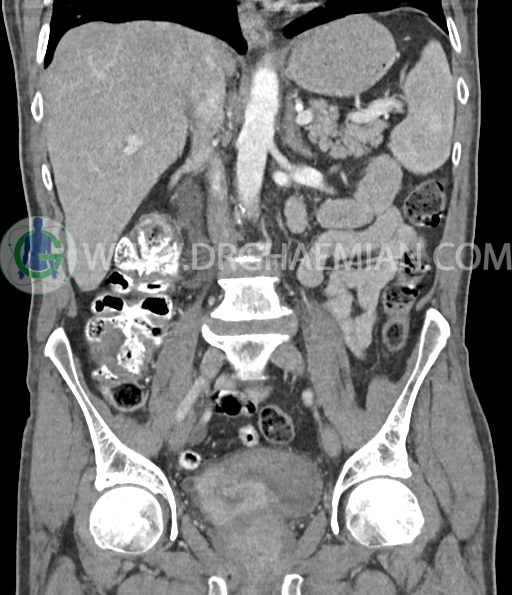

سی تی اسکن لگن و شکم از تشعشعات برای ایجاد تصاویر عرضی مقطعی از لگن و شکم استفاده می کند. در این کیس سرطان سلول انتقالی کلیه، ضایعه کبدی، دیورتیوکولوز، کیست کورتیکال در کلیه چپ، پروستات بزرگ شده، افزایش ضخامت دیواره مثانه دیده می شود.

در سی تی اسکن اسپیرال شکم و لگن با و بدون کنتراست خوراکی و وریدی (مولتی دیدکتور 16 با مقاطع ظریف و بازسازی های ساژیتال و کرونال) :

دیورتیکولوز خفیف پراکنده بیشتر در کولون نزولی رویت شد.

پروستات با دیامتر عرضی 60mmبزرگ تر از نرمال، همراه با bulging لوب مدین به کف مثانه رویت شد.

افزایش ضخامت جداری مثانه مشهود است.

افزایش ضخامت جداری و نامنظمی و لوبولاسیون همراه باenhancement مطرح کننده انفیلتراسیون و ضایعات تومورال در سمت راست ناحیه ترایگون و دیواره لترال راست مثانه دیده می شود که باعث اتساع حالب راست و هیدرونفروز moderate در کلیه راست شده است . این یافته های می توانند مطرح کننده TCC باشند .fat stranding در اطراف مثانه مشهود است. بیرون زدگی توده مانند به قطر 18mm در سمت راست ناحیه ترایگون دیده می شود که می تواند مطرح کننده گسترش اکسترا وزیکولر تومور باشد . لنفادنوپاتی با SAD=10mm درlevel ایلیاک داخلی چپ رویت شد . لنف نود دیگر با SAD= 5mm در همین ناحیه مشهود است. با توجه به این یافته ها stage احتمالی تومور T3، N1 or N2 می باشد .